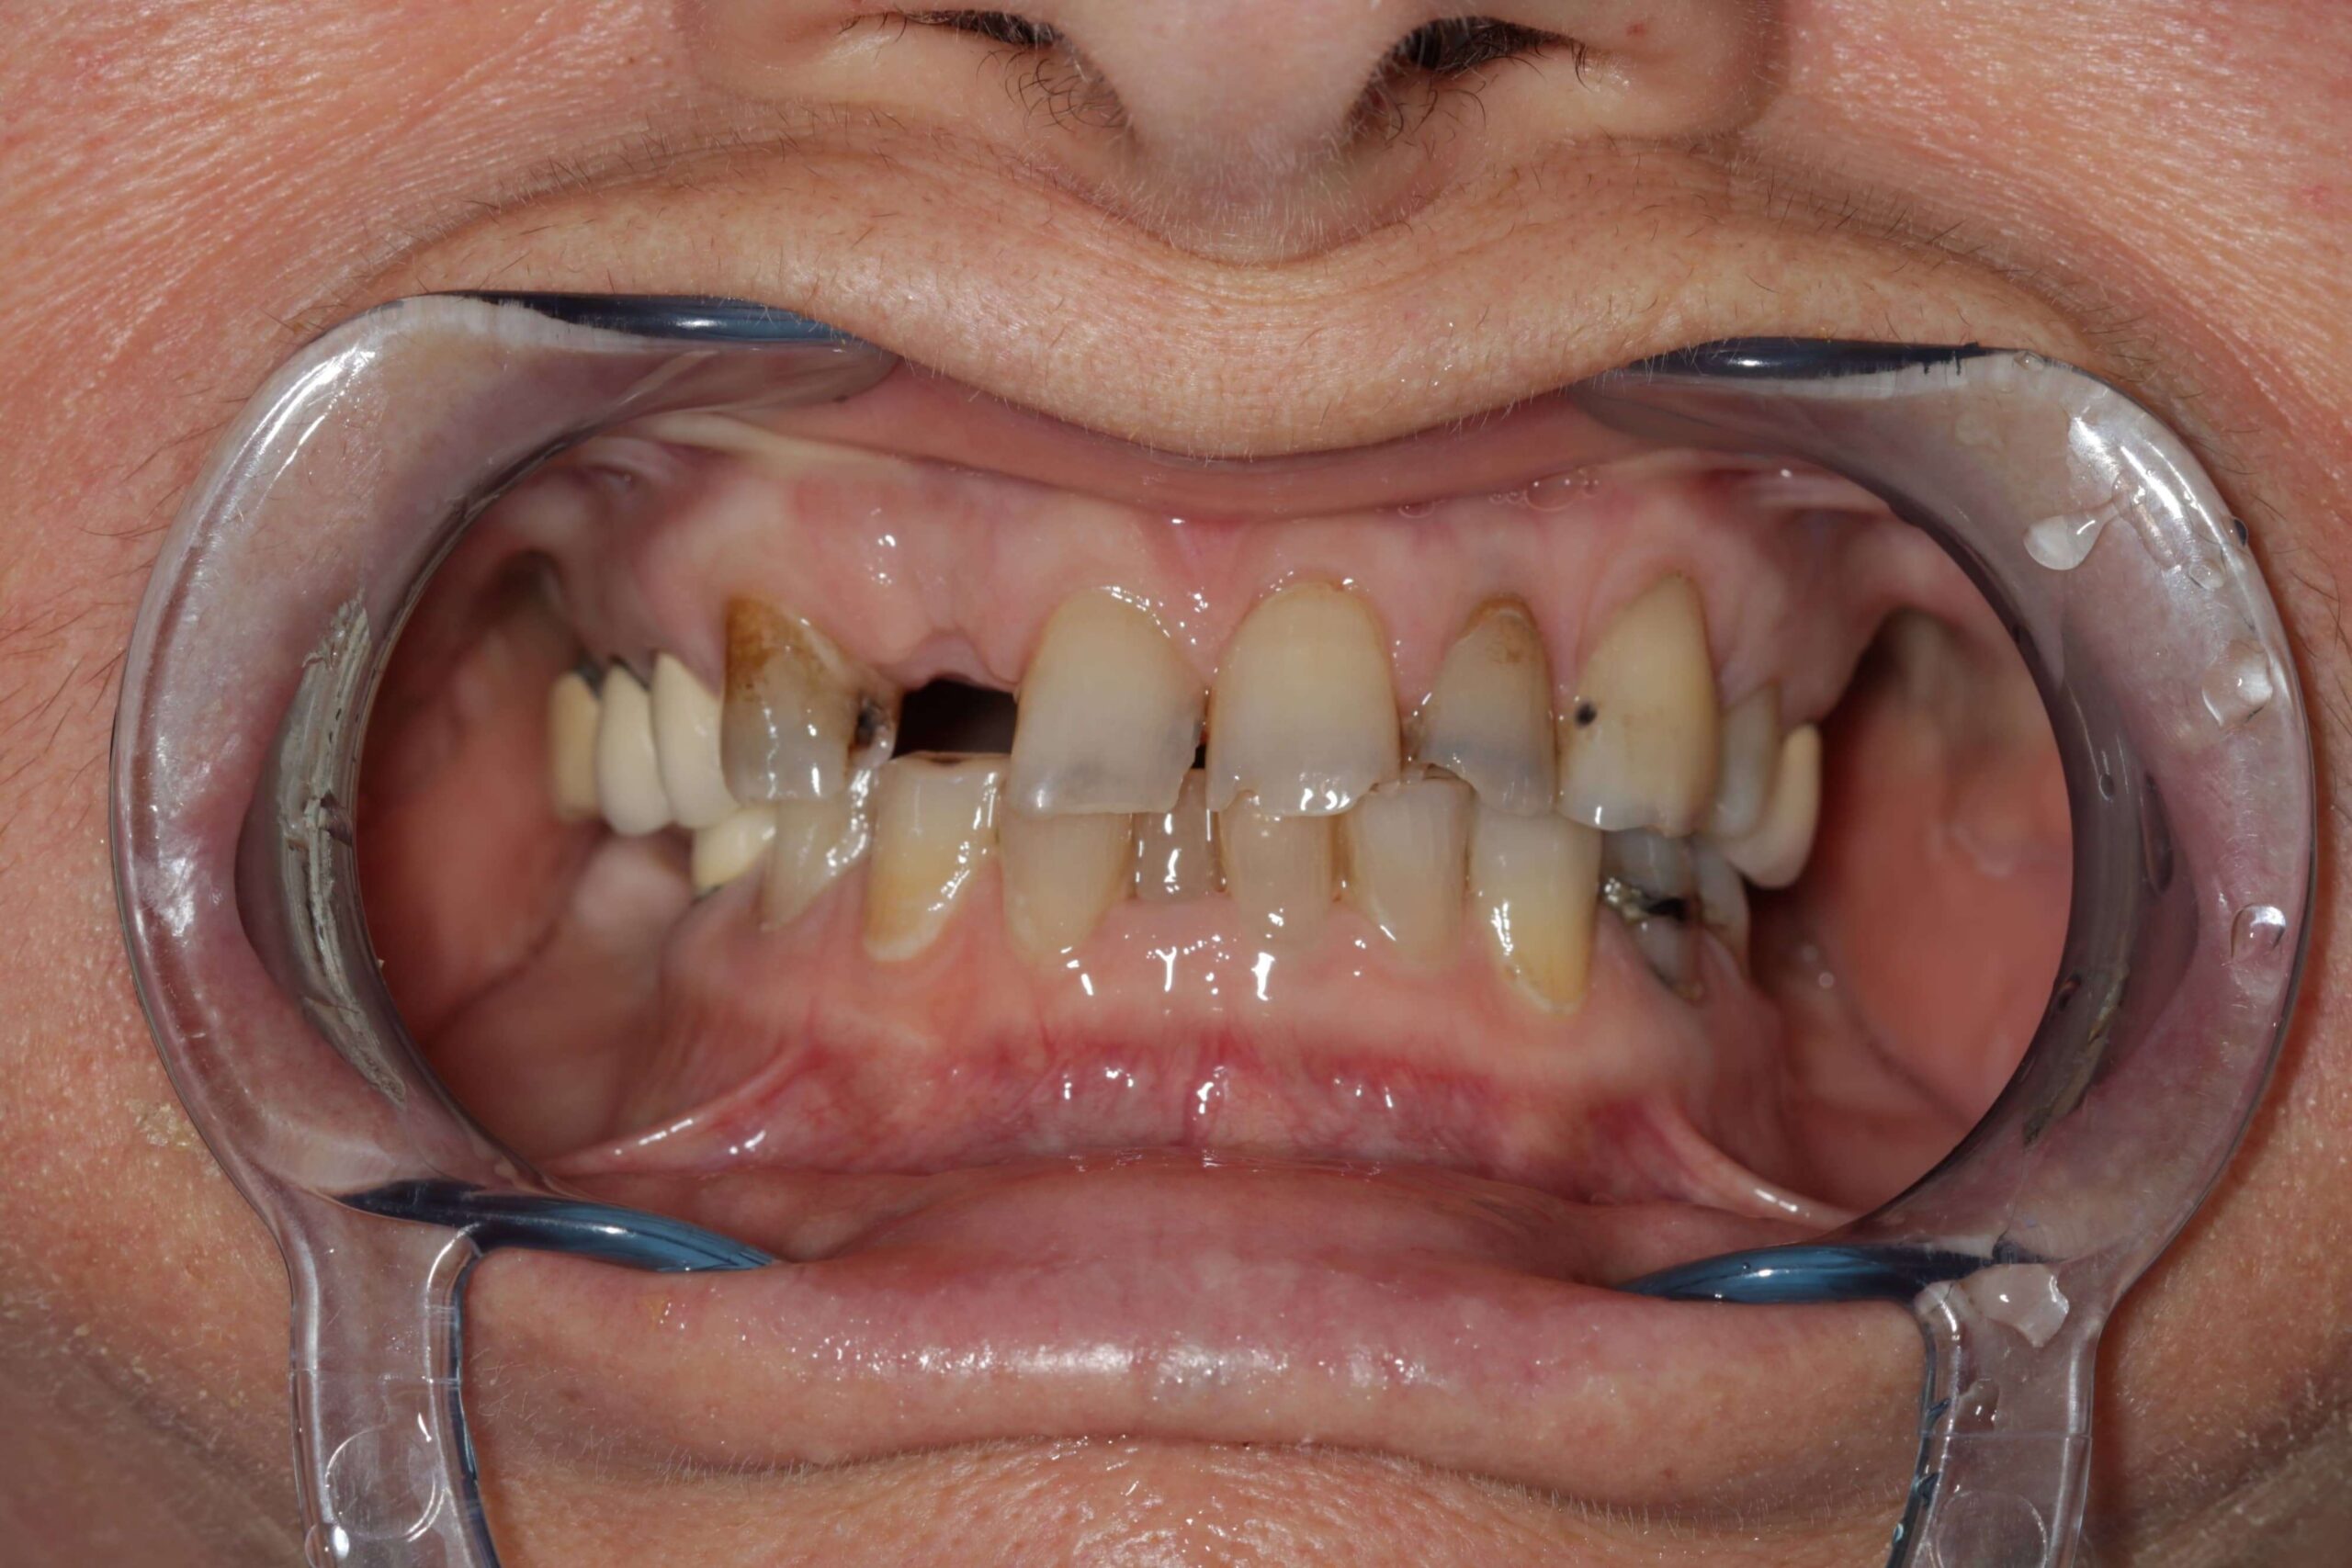

- Nem megfelelően kialakított fogpótlások: rosszul illeszkedő koronák, hidak vagy kivehető pótlások hosszú távon megváltoztathatják a harapási viszonyokat, túlterhelhetik az állkapocsízületet, és funkcionális egyensúlyzavart idézhetnek elő. Ez gyakran vezet feszüléshez, rágás közbeni fájdalomhoz vagy ízületi kattogáshoz.